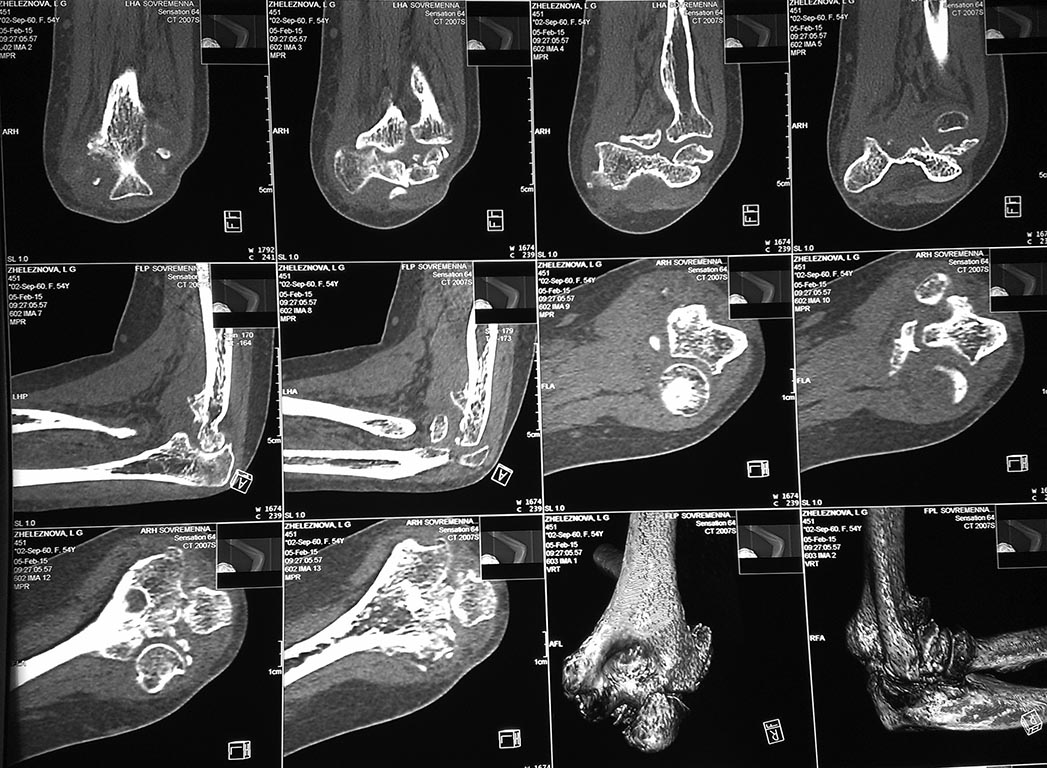

У женщины 54 лет имеются последствия закрытого вывиха костей предплечья...

Травма 08.11.14 г., окончательное вправление лишь 10.11.14 г., тогда же

появились признаки нейропатии локтевого нерва, они остаются до сих пор.

Движения в суставе качательные, практически анкилоз в положении 90 град.

Снимки КТ в приложении. Уважаемые травматологи-ортопеды! Что делать в

такой ситуации? Эндопротез? Релиз? Ничего?